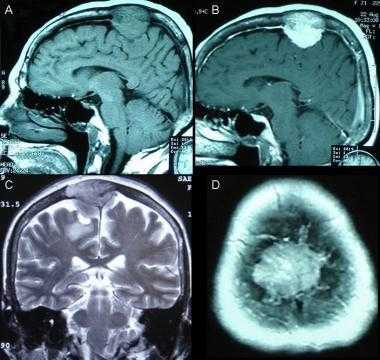

Фалькс-менингиома на МРТ.

А: на Т1-взвешенном МР-изображении отмечается солидное образование, характеризующееся изоинтенсивностью по отношению к твердой мозговой оболочке, инвазией в кость и сдавлением теменных зон коры.

В: На Т1-взвешенном МР-изображении с контрастным усилением видна частично контрастируемая опухоль.

С: На корональном Т2-взвешенном изображении видно изоинтенсивное образование, что соответствует плотной ткани. Такая картина характерна для фибробластных менингиом.

D : На Т1-взвешенном МР-изображении с контрастным усилением визуализируется гиперинтенсивное образование внутри мозгового вещества кости.

Метастазы головного мозга на МРТ. Фото. Определяются множественные метастазы в мозг при раке легкого: слева в режиме Т1-ВИ в виде гипоинтенсивных образований, справа — в режиме Т2-ВИ виде множественных участков повышенного сигнала, окруженных зоной перифокального отека. У пациента подтверждена первичная опухоль легкого.